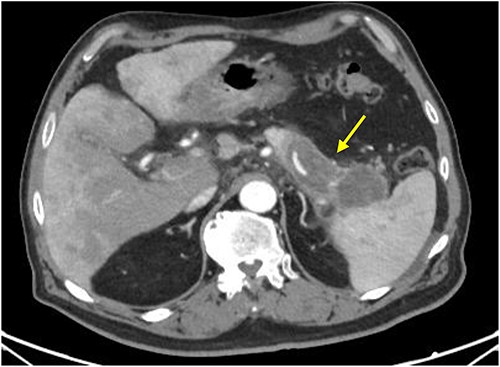

Initial imaging with computed tomography (CT) of the chest, abdomen, and pelvis with IV contrast identified a hypoenhancing infiltrative pancreatic tail mass with central necrosis, as seen in Fig. 1. Given the diffuse hypodensity and without evidence of metastatic disease, findings were favored to represent pancreatitis with pancreatic necrosis. Magnetic resonance cholangiopancreatography (MRCP) was subsequently obtained which again revealed findings favored to be pancreatic necrosis rather than malignancy, as seen in Fig. 2. He then underwent an endoscopic retrograde cholangiopancreatography, which found a common bile duct stone which was extracted, as well as a high-grade benign-appearing ampullary stenosis, which was brushed and stented. The patient’s hyperbilirubinemia unfortunately failed to resolve following biliary ductal decompression. His highest documented total bilirubin was 24 mg/dl, largely from a direct component. Finally, he underwent an endoscopic ultrasound (EUS), which identified a mass in the body and tail of the pancreas advancing into the second portion of the duodenum with extensive surrounding ascites. Two fine-needle biopsies were taken, which resulted positive for invasive adenocarcinoma.

CT scan with IV contrast: axial image showing hypoenhancing infiltrative pancreatic tail mass with central necrosis (arrow), measuring 8 × 3 × 4 cm with adjacent stranding and mass abutting the spleen that appears to completely encase the splenic artery and vein.